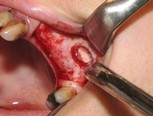

If your jawbone is found suitable for implantation, then the treatment may start even on the same day. (If your jawbone is found unsuitable as is, then it needs to be augmented preceding treatment: see the FAQ menu). The implantation procedure begins with the insertion of one or more titanium post(s) into the jawbone, along with small caps (abutments) fastened to the implants, which provide support for the future prostheses. The gum is then stitched up with absorbable stitches that dissolve naturally in a few weeks. The entire procedure is performed under local anaesthesia.